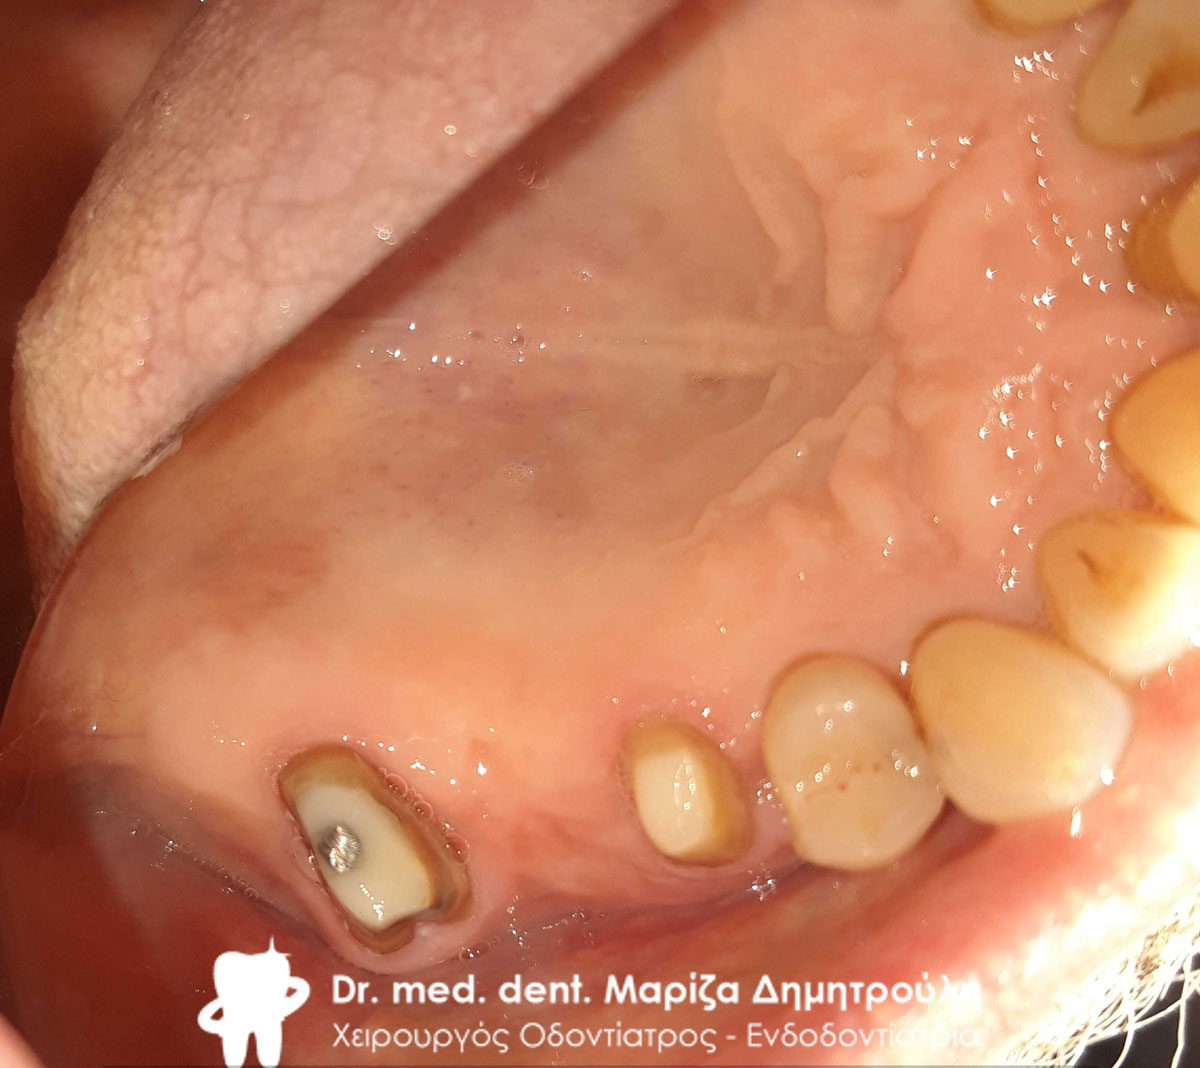

Κλινική εικόνα του δοντιού μετά τον εκτροχισμό του

Περιστατικό – Ολοκεραμική στεφάνη / θήκη ζιρκονίου στην αριστερή πλευρά της κάτω γνάθου